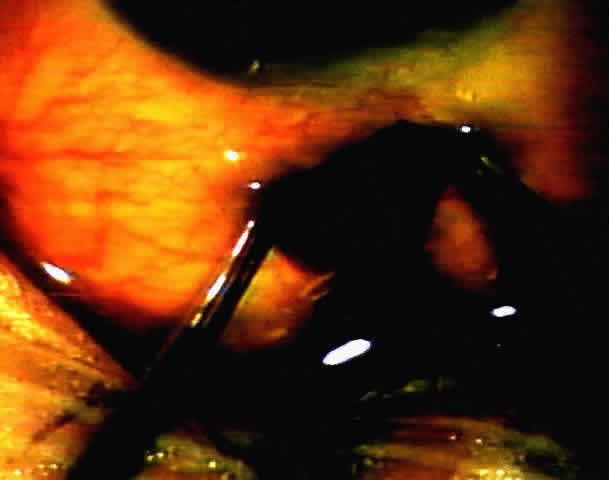

Goniosynechialysis

In past decades, the high incidence of complications and low success rate of goniosynechialysis was discouraging. The procedure was performed in the 1950s and 1960s, but with only balanced salt solution available to maintain the anterior chamber and to control bleeding, it was technically difficult.41 This procedure was recently re-evaluated by Campbell and Vella,42 introducing the technical advantage of the newly developed viscoelastic substances. By keeping the anterior chamber formed and inhibiting bleeding mechanically, viscoelastics facilitate the surgical reopening of angles with extensive synechial closure. They recommend anterior chamber deepening using a viscoelastic substance. The peripheral anterior synechiae are then separated from the trabecular meshwork using a smooth-tipped cyclodialysis spatula. Good candidates for this procedure are eyes with fairly healthy optic discs and less than 6 months of synechial closure.